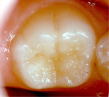

これは、萌出間もない六歳臼歯の咬合面の溝にフッ化物含有のセメントなどで一時的に塞ぎ、う蝕予防のために行う方法で、はっきりとターゲットを絞った永久歯のう蝕予防法である。

なお、シーラントは破折したり、外れやすいので定期的に管理の必要性があり、シーラントが取れたままだと逆にう蝕になりやすくなるので注意が必要である。

シーラント前              シーラントをした状態